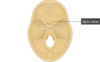

- *Optic canal** tramsmits the optic nerve and opthalmic artery.

- *Superior orbital fissure** transmits the lacrimal, frontal, trochlear, oculomotor, nasociliary, abducent nerves with the sup. opthalmic vein

- *Foramen rotundum:** Maxillary nerve to pterygopalantine fossa

- *Foramen ovale:** Large sensory root and small motor root of mandibular nerve

- *Formaen Spinosum:** MMA & vein (from the infratemporal fossa into the cranial cavity)

- *Foramen lacerum:** Carotid artery

- *Sulcus chiasmatis** related to optic chiasm and lead sto optic canal on either side

- *Sellae Turcica** lodges the pituitary gland

Foramen Magnum:Occupies central area of floor, transmits the medulla oblongata, the spinal portion of CNXI and the two vertebral arteries

Hypoglossal canal: hypoglossal nerve

Jugular foramen: CN IX, X & XI and sigmoid sinus (NB Sigmoid sinus becomes the internal jugular vein)

Internal acoustic meatus: Transmits the vestibulocochlear nerve and motor + sensory roots of the facial nerve.